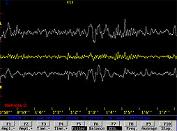

Três replays em tempo real

As telas abaixo podem ser vistas em velocidade de tempo real ou em avanço rápido.

Display linear de 3 linhas

As imagens abaixo mostram o hemisfério esquerdo acima e o direito abaixo. O tempo está no eixo horizontal e a intensidade da onda no eixo vertical. A linha amarela no centro representa o equilíbrio e será reta quando os dois hemisférios estiverem fazendo as mesmas coisas ao mesmo tempo. É possível observar uma tela com zoom para até 2 segundos ou em amplitudes de até 10 segundos para observar tendências mais longas.